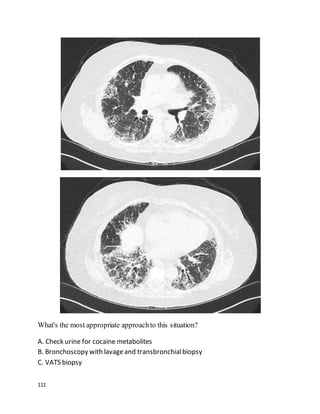

You receive an email from a colleague asking for a "curbsideconsult." You haven't

heard the story or your colleague's question yet, but to frame your thinking, you

quickly glance at the images she's attached to the email.

Based on these images, what's the most likely clinical scenario?

A. A 50-year old man with a mass in the head of the pancreas.

B. A 66-year old man with progressive dyspnea on exertion, leg edema, and

longstanding hypertension.

C. A 48-year old woman treated for malignant melanoma 2 years ago.

D. A 24-year old woman with HIV-AIDS, 4 weeks of dyspnea and dry cough,

SaO2 of 88% on ambient air, non-adherent with Bactrim prophylaxis.

E. A 60-year old chicken farmer with progressive dyspnea and a positive

hypersensitivity panel.

We feelthat A is the best answer.